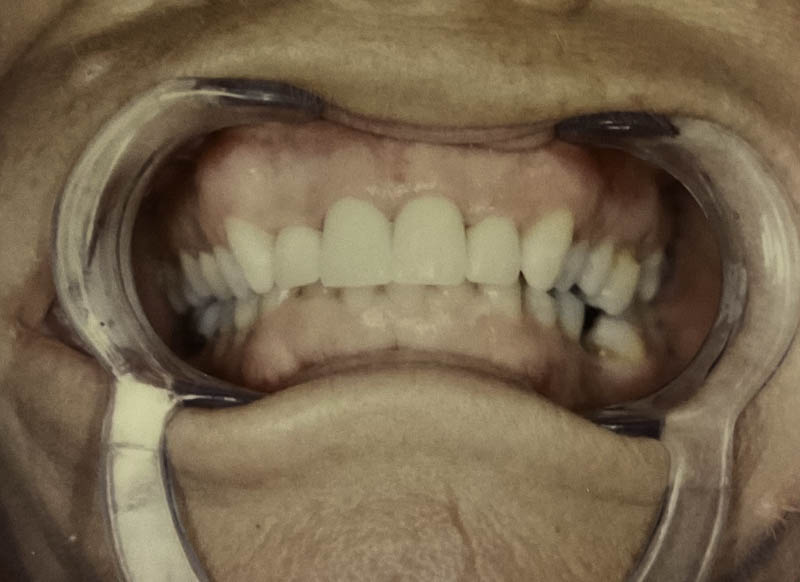

Before

After

Custom Cosmetic Crowns

Case Highlight